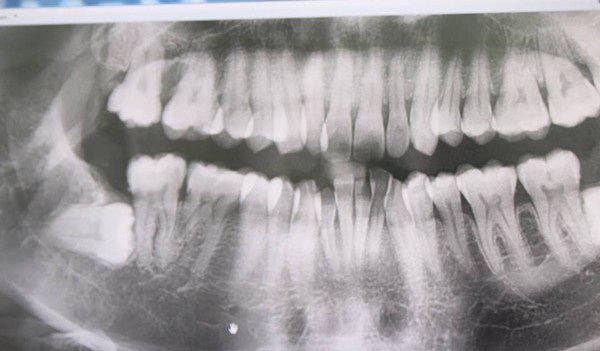

Phụ nữ trong độ tuổi sinh đẻ cần nhổ răng khôn mọc lệch trước khi có ý định mang bầu. Trong ảnh, răng khôn mọc ngang, húc vào răng số 7